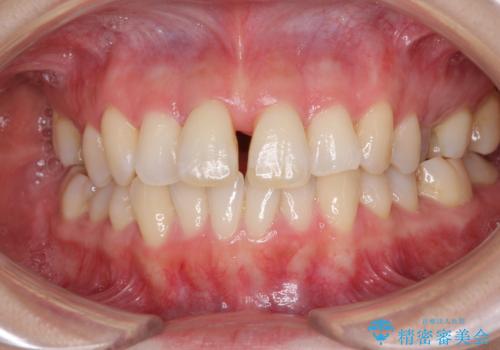

- 奥歯の咬み合わせを気にして来院された患者様です。

上顎骨の幅が下顎骨よりも小さいので、拡大装置により骨幅を広げて上下関係を改善し、その後インビザラインにて歯並びを整えることとしました。

上下の骨幅を改善したことで、スムーズに歯列矯正を行うことができました。

奥歯の咬み合わせを改善する必要があったため、治療は長期化しましたが、きっちりと仕上げることができました。